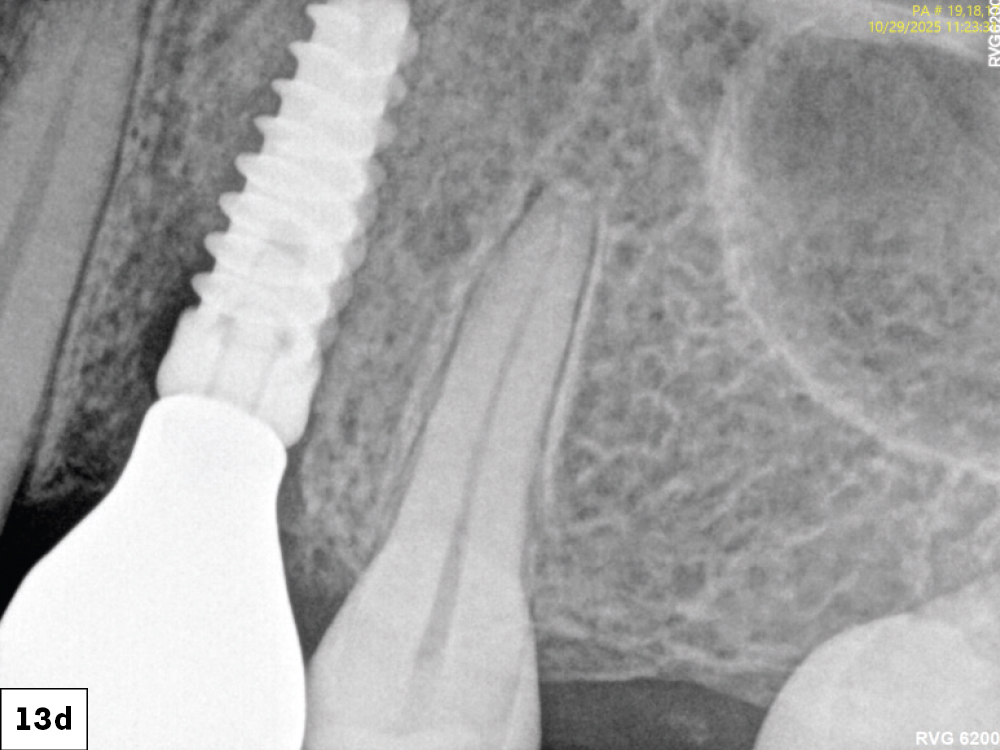

Figures 13a–13d: At the one-week follow up, both implants demonstrated excellent integration with healthy peri-implant tissues and no inflammation. At eight weeks, mature keratinized mucosa framed the zirconia crowns with stable crestal bone levels and ideal emergence profiles were confirmed radiographically.